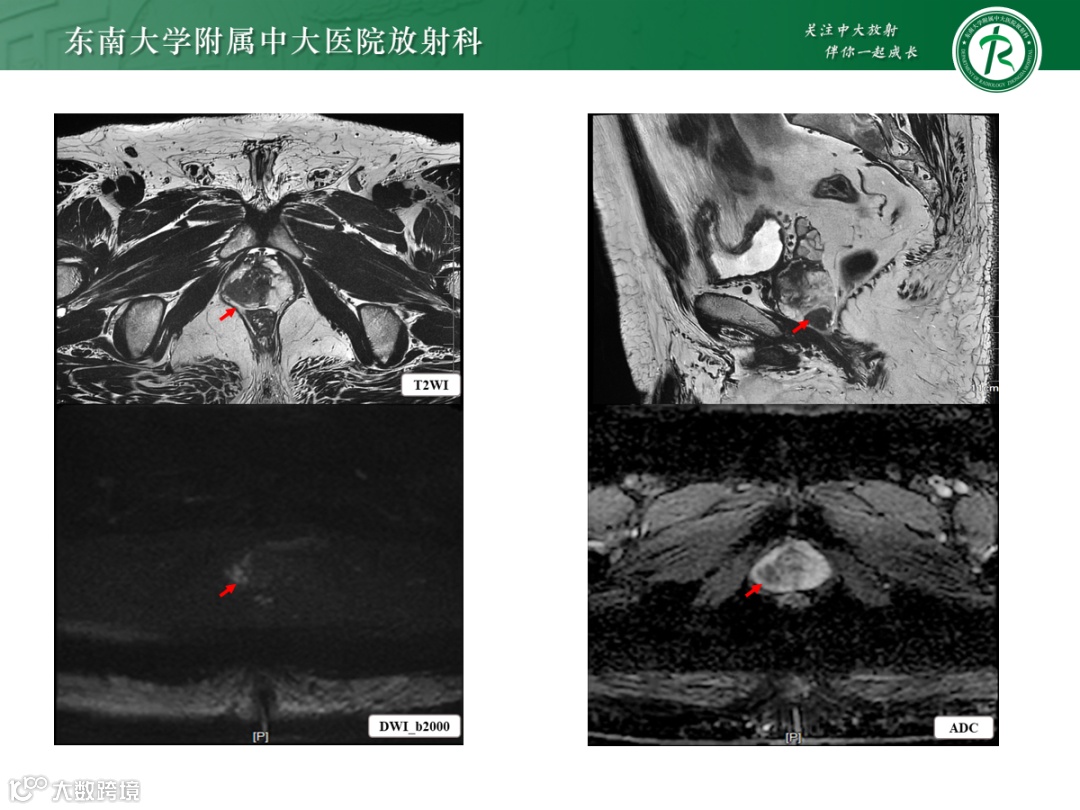

影像学表现